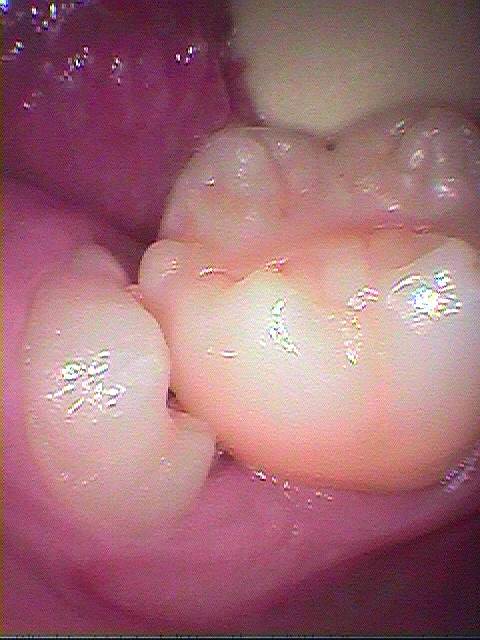

右下の親不知の抜歯 水平埋伏歯の難抜歯|お知らせ |広島市安佐南区の歯科医院 右下の親不知の抜歯 水平埋伏歯の難抜歯 トップ お知らせ・ブログ お知らせ 右下の親不知の抜歯 水平埋伏歯の難抜歯 右下の親不知の抜歯 水平埋伏歯の難抜歯 わずかに親知らずが見えています 磨けないですし、良いことがない親知らずになります 虫歯、歯周病とあらゆるトラブルが引き起こされます このようにかなり骨植もよく真横に横たわっていました 歯間部を分割していきました このように切開を加えることなく歯冠部を分割、抜歯を行っています ですから抜歯窩からもほとんど出血がありません 縫合して終了となります 腫れないように少し開けています Web診療予約 初めての方へ 選ばれ続ける理由 院内設備について 歯が痛いしみる一般歯科 歯がぐらぐらする歯周病 健康な歯を保ちたい予防歯科 子供の虫歯予防をしたい小児歯科 銀歯をセラミックに審美歯科 白い歯を目指しませんか?ホワイトニング 矯正専門医がいるので安心矯正歯科 抜けた歯を補いたいインプラント・入れ歯 医院案内 スタッフ紹介 メリィハウス歯科クリニックオフィシャルホームページ ラベンダー歯科クリニックオフィシャルホームページ お知らせ・ブログ ホーム 診療科目 一般歯科 歯周病治療 予防治療 小児歯科 審美治療 ホワイトニング 矯正歯科 入れ歯・インプラント マウスピース矯正 初めての方へ 院長・スタッフ 設備紹介 医院案内・アクセス メニューを閉じる